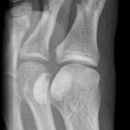

D1 Wachstumskerbe